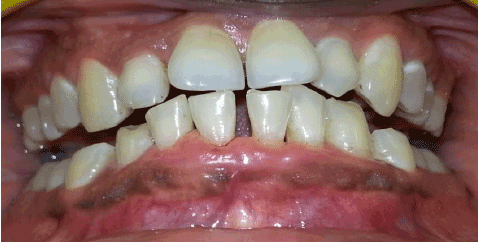

治疗计划包括口腔卫生指导,专业的口腔预防和医疗咨询,以考虑可能改变高血压药物。患者接受了I期牙周治疗,包括全口洁牙、根规划和0.2%洗必泰溶液口内冲洗。在一期治疗一个月后,牙龈过度生长的情况显著减少,出血评分也有显著改善,斑块评分和结石评分,但过度生长并未完全消退(图3)。患者转至医生,根据医生的建议,将氨氯地平改为氯沙坦/氢氯噻嗪联合用药。患者接受严格的口腔卫生治疗,3个月后复查。在召回时,牙龈过度生长完全缓解,下前牙探测袋深度小于4毫米(图4)。目前,患者处于维护期,每隔3个月定期召回。

图4:三个月后牙龈过度生长完全缓解